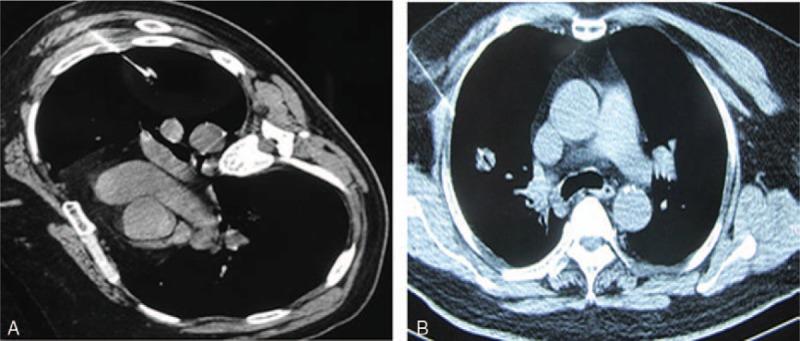

计算机断层扫描引导下经皮穿刺针吸活检术用于直径小于20毫米的孤立性肺结节

Computed tomography-guided percutaneous transthoracic needle biopsy for solitary pulmonary nodules in diameter less than 20 mm.

To evaluate the diagnostic value of computed tomography (CT)-guided percutaneous lung biopsy for solitary pulmonary nodules (SPN) < 20 mm.A total of 248 patients who were diagnosed a SPN of < 20 mm underwent CT-guided percutaneous transthoracic needle biopsy were reviewed.Specimens of 248 patients were obtained successfully. Around 174 cases were proved to be malignancies and 74 cases of benign lesions by biopsy. About 178 malignancies (71.8%) and 70 benign lesions were proved by surgery and clinical course. The diagnostic accuracy was 96.8%. The diagnostic accuracy of large nodules group (>10 and < 20 mm) was 99.3%, higher than 93.5% of small nodules group (≤10 mm) with statistical significance. The incidence of phenmothorax and hemorrhage was 16.1% and 6.8%, respectively. No death-related complications happened. The incidence of phenmothorax was related to puncture times (P = .013) and the length of puncture needle in lung tissues (P = .019).CT-guided percutaneous lung biopsy for SPN of < 20 mm is an efficient and safe diagnostic method.

评估计算机断层扫描(CT)引导下经皮肺穿刺活检对直径<20mm的孤立性肺结节(SPN)的诊断价值。回顾性分析248例诊断为直径<20mm的SPN患者接受CT引导下经皮经胸针吸活检的情况。成功获取了248例患者的标本。活检证实174例为恶性病变,74例为良性病变。手术及临床病程证实178例恶性病变(71.8%)和70例良性病变。诊断准确率为96.8%。大结节组(>10且<20mm)的诊断准确率为99.3%,高于小结节组(≤10mm)的93.5%,差异有统计学意义。气胸和出血的发生率分别为16.1%和6.8%。未发生与死亡相关的并发症。气胸的发生率与穿刺次数(P = 0.013)及穿刺针在肺组织中的长度(P = 0.019)有关。CT引导下经皮肺穿刺活检对直径<20mm的SPN是一种高效、安全的诊断方法。